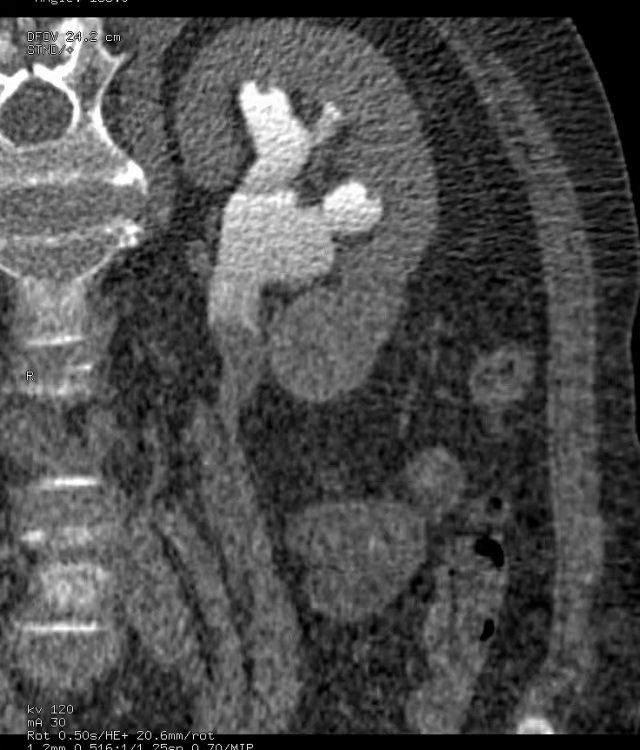

上图所示:体检B超示(右)肾积水,行CT尿路造影检查。左图示平扫后重建示(右)肾囊肿向肾盂内突出。右图示,静脉注入造影剂、经过一定时间延迟后,(右侧)输尿管起始处造影剂充盈良好,肾盂内囊肿内未见造影剂填充。 (二)肾外肾盂: 正常人肾盂大多位于肾窦内,成为肾内肾盂;少数位于肾窦外,成为肾外肾盂。肾外肾盂属于正常肾盂的一种情况,可见于任何年龄。